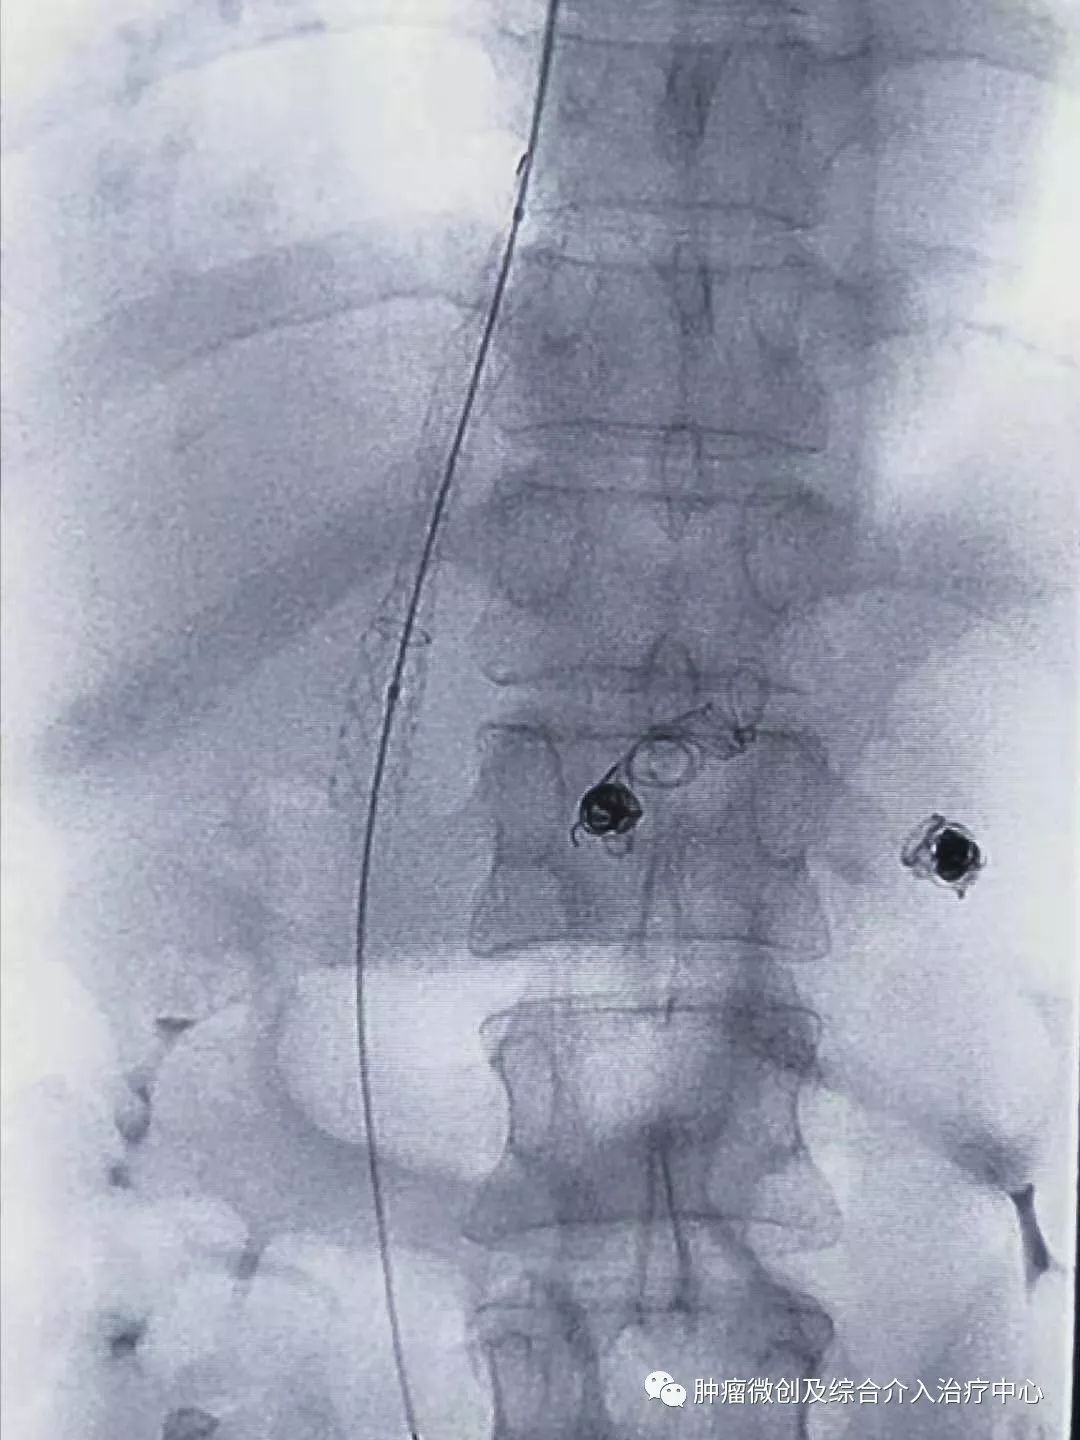

栓塞消化道出血责任血管:

球囊扩张静脉-门脉支架:达到门脉-体静脉充分分流目的

再次造影可见:门脉血流流向-体静脉达到分流目的,术前侧压力42,术后25,门脉压力明显降低,达到防止再次出血目的。